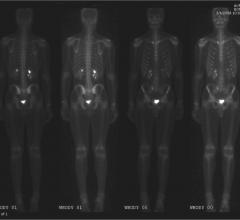

Post-treatment surveillance with molecular imaging could mean the early start of a new, life-saving treatment for non-Hodgkin lymphoma (NHL), said researchers at the 2015 Annual Meeting of the Society of Nuclear Medicine and Molecular Imaging (SNMMI).